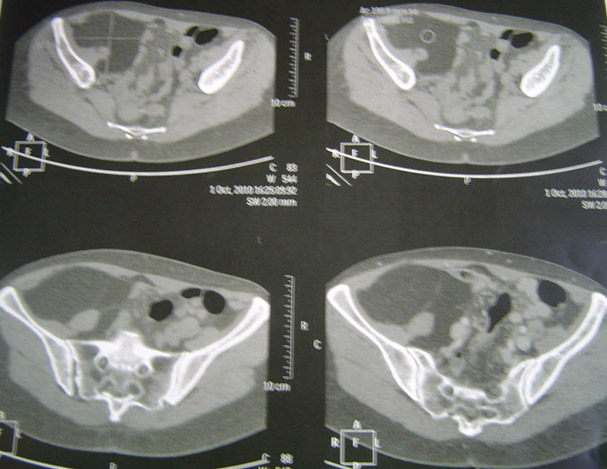

Cas Clinique

Une deuxième chance ?

Dr Jacques Fechtenbaum Hôpital Cochin - Paris

Le 03 novembre 2010, Mr F., 24 ans, s’est défenestré du 4ème étage.

Adressé en urgence dans un service d’orthopédie, la fracture du calcanéum a été ostéosynthésée.

La fracture de la vertèbre L1 a également été chirurgicalement immobilisée.

Quinze jours après, il marche normalement, sans boiterie, sans séquelle.

Il n’a pas d’atteinte viscérale du petit bassin, pas de lésion urologique, pas

Des difficultés à fléchir la cuisse

Mme K., née en 1950, vient vous consulter pour une incapacité à soulever le membre inférieur droit. Depuis deux ans, elle doit utiliser ses mains pour lever sa cuisse.

A l’examen clinique, l’articulation coxo-fémorale droite est normale, les aires ganglionnaires sont normales, le réflexe rotulien droit est normal, le muscle psoas est coté à 3 + et elle présente des difficultés à la flexion de la cuisse. Il n’existe pas de syndrome rachidien.

Quel examen complémentaire auriez-vous demandé ?